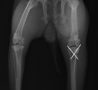

症例 骨端板骨折 ウサギ 4ヶ月齢 ♀ 稟告 来院15分前、すの...